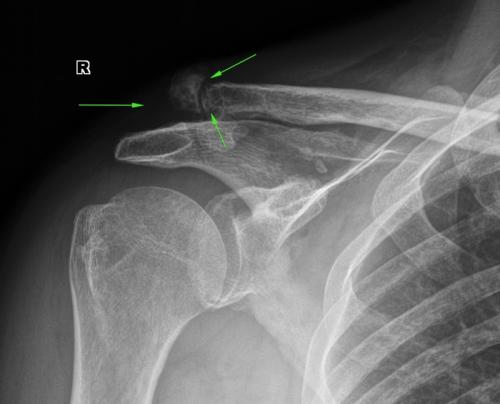

На этой недели (хотя еще только четверг) приходили два уникальных человека - с переломами, но не знающие об этом. Первый был с переломом ключицы, который обнаружили случайно - снимали легкие на мед. осмотре, ключицы попадают в кадр - и там перелом. Пациент говорит - упал дней 15-20 назад, плечо болит и болит, ну, думаю, поболит и пройдет. Даже в больницу не ходил. Снимаем, а там такая красота:

Перелом уже начал помаленьку срастаться, но руку все равно необходимо фиксировать. Отправили к травматологу.

Еще одна ключица, только уже со сформировавшимся суставом. Тут у человека будет явное нарушение осанки и другие проблемы. Смотрите в сравнении с противоположной ключицей.

Ложный сустав ключицы, но с краю: